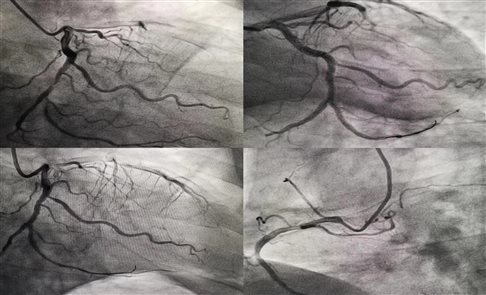

患者病情稳定后,急诊科立即联系中心医院胸痛中心专家,沟通发病经过及抢救过程,转中心医院进一步治疗。因为有了前期的沟通协调,120到达中心医院胸痛中心后,患者第一时间得到接诊。中心医院医生立即给予患者冠脉造影,造影显示溶栓有效,后经冠脉支架植入手术后,病人最终转危为安!